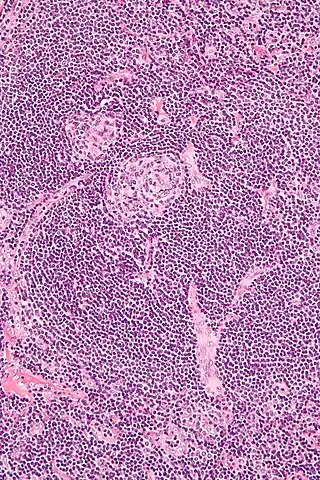

![]() Micrografía de la variante vascular hialina. | ||